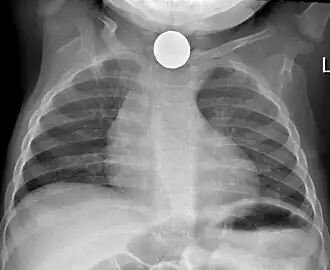

Chest X-ray showing a Canadian dollar coin in the esophagus of a young child

Prior to undertaking endoscopy, attempts should be made to locate the foreign body with x-rays or other non-invasive techniques.[1] For radio-opaque objects, x-rays of the neck, chest and abdomen can be used to locate the foreign body and assist endoscopy.[9] Alternative approaches, including the use of metal detectors, have also been described.[10]

X-rays are also useful for identifying the type of foreign body ingested and complications of foreign body ingestion, including mediastinitis and perforation of the esophagus.[1]